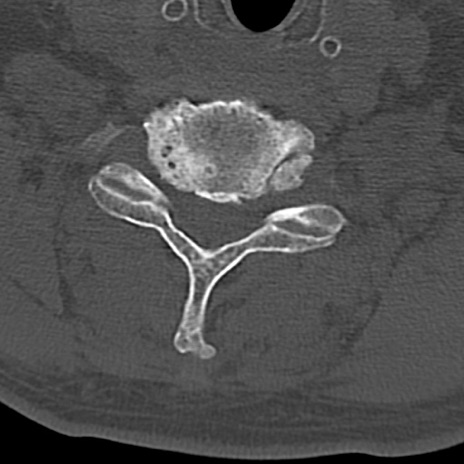

頚椎CT

横断像